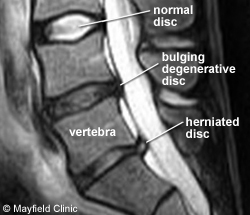

For those wondering, this is what a herniated disk looks like under an MRI scan:

I had one in 2015 that caused me a lot of back pain. It led to my changing my workout routine, researching what actually made sense. I was previously relying on just the elliptical trainer, but that's bad for you. Doing only low-to-moderate intensity cardio is bad for you.

You should all take care of your health, particularly those of you with a desk job. That could mean swimming, or skiing, or yoga, or pilates, or tennis, or weight training. It has to be something you enjoy or you won't do it. It should also be vigorous physical activity: that rules out jogging, golf, and softball.